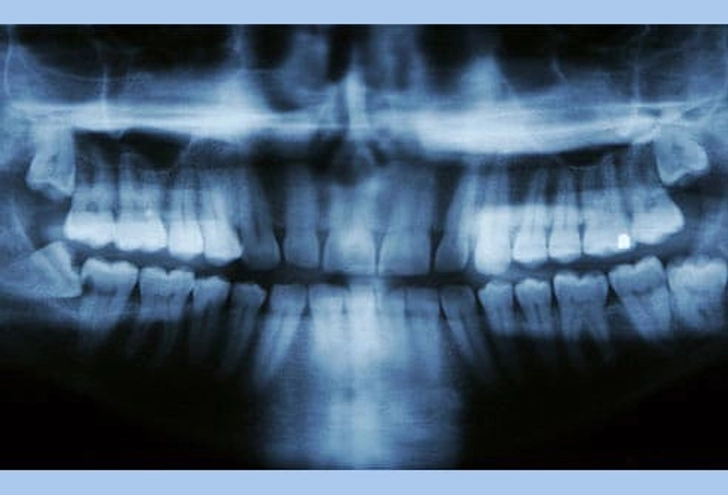

۵. دندان نهفته (Impacted Teeth)

دندانهای دائمی که درست رویش نمیکنند «نهفته» نام دارند. این حالت معمولاً وقتی رخ میدهد که دندان به دندان کناری، استخوان یا بافت نرم گیر کرده باشد. اگر مشکلی ایجاد نکند، ممکن است دندانپزشک توصیه کند همانطور باقی بماند. اما در صورت درد یا احتمال بروز مشکل، دندان توسط جراح فک و صورت خارج میشود.

۱۳. مشکلات دندان عقل

بیشتر افراد (۹۰٪) حداقل یک دندان عقل نهفته دارند. این دندانها میتوانند باعث پوسیدگی، آسیب به دندانهای کناری و بیماری لثه شوند. رویش دندان عقل معمولاً بین ۱۷ تا ۲۵ سالگی رخ میدهد. دندانپزشک باید روند رشد را پیگیری کند و در صورت مشکل، دندان کشیده میشود.